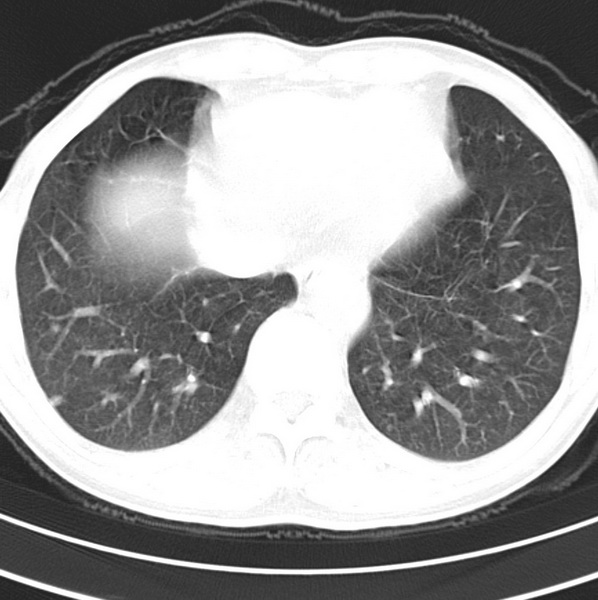

男、48、咳嗽。

胸片示双肺纹理紊乱,行胸部ct检查。

右肺下叶基底段结节影,双肺粟粒样阴影,ct值测量约-20hu左右,可能不准。

层厚层距为4mm左右,病灶轴面最大径约1cm左右。